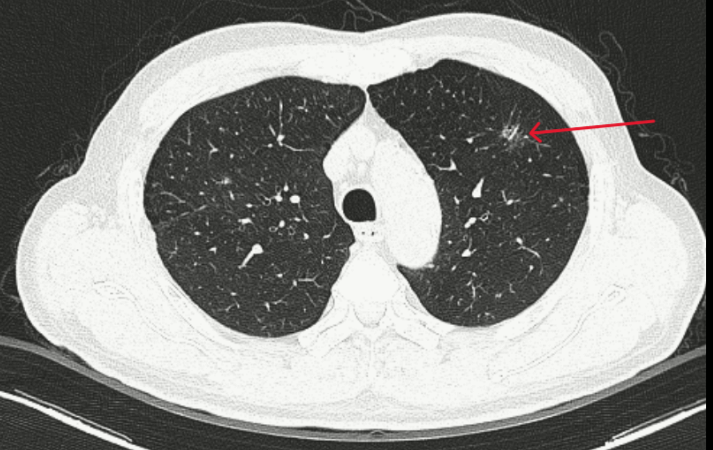

Thùy trên phổi trái có đám tổn thương kính mờ, bờ tua gai kích thước 10x13mm - Ảnh: BVCC.

Trong quá trình chụp CT kiểm tra, bác sĩ tình cờ phát hiện một tổn thương dạng kính mờ thùy trên phổi trái, nghi ngờ ác tính nên chuyển bệnh nhân sang Trung tâm Y học hạt nhân và Ung bướu để đánh giá tiếp.

Các xét nghiệm máu, sinh hóa, đông máu đều trong giới hạn bình thường; marker Cyfra 21-1 tăng nhẹ. Kết quả chụp CT ngực cho thấy tổn thương kính mờ bờ tua gai thùy trên phổi trái, CT bụng ghi nhận giãn đài bể thận và sỏi niệu quản.

Tổn thương phổi được phân tích bằng hệ thống AI, kết quả cho thấy xác suất ác tính lên đến 97%. Hội đồng chuyên môn quyết định phẫu thuật nội soi cắt thùy phổi và nạo vét hạch.